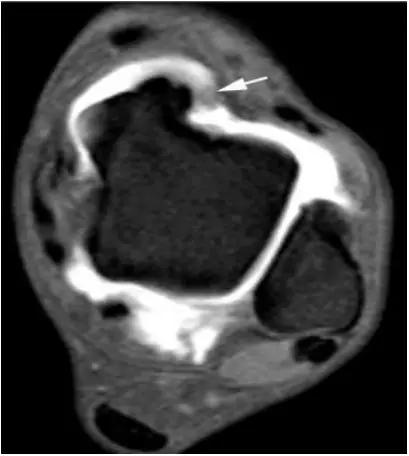

三角籽骨综合征

- 踝后部疼痛其常见的三种原因是眼后滑囊炎、长屈肌肌腱炎和三角骨综合征。

- 三角籽骨综合征(距骨后三角骨综合征)又称后踝撞击综合征或距骨受压综合征是后踝关节慢性反复疼痛常见的病因之一。

- 距骨后三角骨,是常见的变异,是踝部最多见的副骨,约占8.1% ,是由距骨后突独立骨化中心骨化而成。与距骨有软骨相连或完全分开,也可表现为独立的不规则骨块。三角骨与距骨后突外侧结节腓侧隐窝相对应。三角骨可以成对存在,还可以与外侧结节融合,形成单一的突起,并可与距骨融合或形成关节。三角骨与其它副骨一样,可妨碍足的运动,同时本身亦可受外界影响发生无菌性坏死。

三角籽骨综合征并跟腱滑囊积液